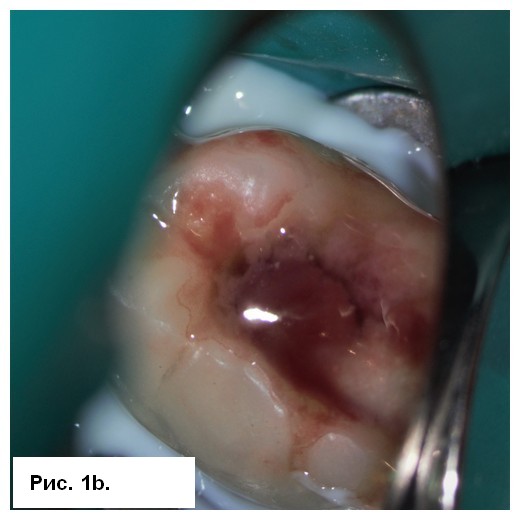

На рентгенограмме (рис. 1а) отмечались большие радиолюсцентые очаги на обоих корнях. Был поставлен диагноз: «некроз пульпы и острый апикальный абсцесс зуба 46». После консультации со стоматологом-ортопедом было принято решение провести эндодонтическое лечение с доступом к корневым каналам через существующую коронку. После вскрытия полости зуба было получено большое количество гнойного отделяемого с кровью (рис. 1b). Дренажу благоприятствовала ирригация 3 % NaOCl (рис. 1с), проведена инструментация корневых каналов системой 2Shape (MICRO-MEGA) и определена рабочая длина (рис. 2.а). Корневые каналы были заполнены гидроксидом кальция.